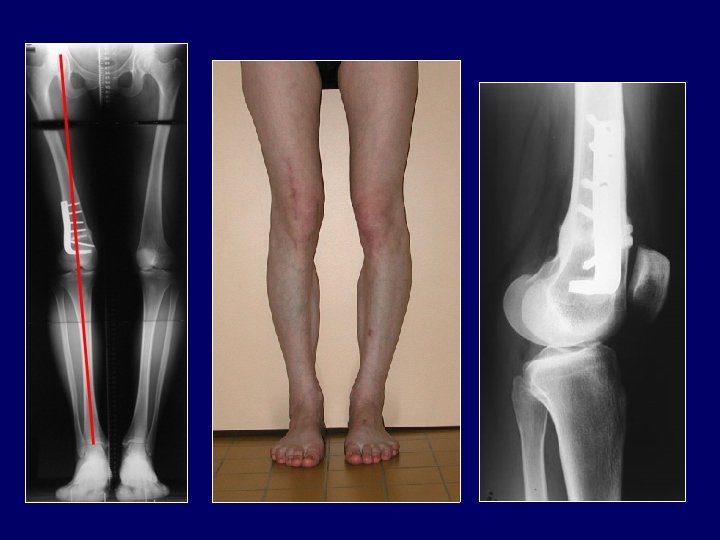

2/ Exemple de flexum Flexum majeur chez une femme présentant un polydystrophie avec atteinte des 2 hanches et arthrose du genou Le genu varum justifie une ostéotomie de valgisation On en profitera pour corriger aussi le flexum par une fermeture antérieure ou une ouverture postérieure

L’ostéotomie de valgisation a été faite par ouverture interne Le flexum a été corrigé par un coin plus épais en arrière